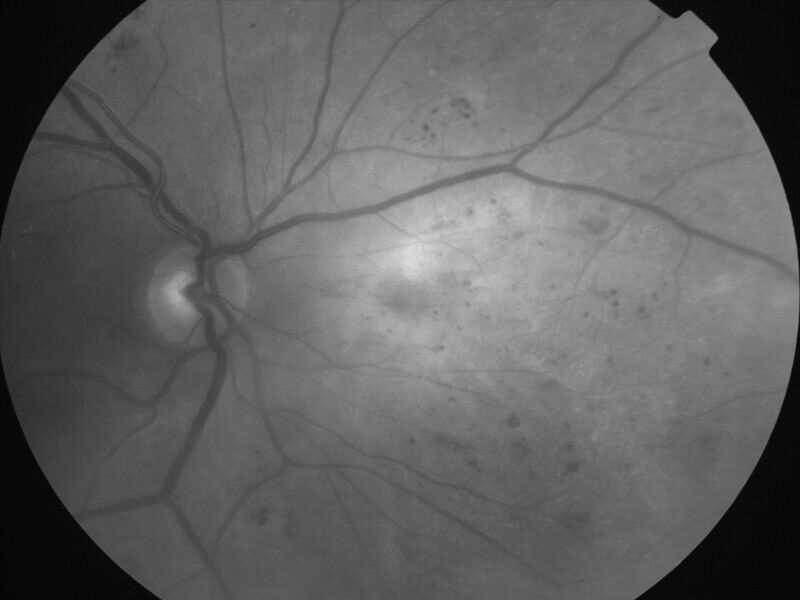

rétinopathie diabétique pré-proliférante

IM000004.jpg